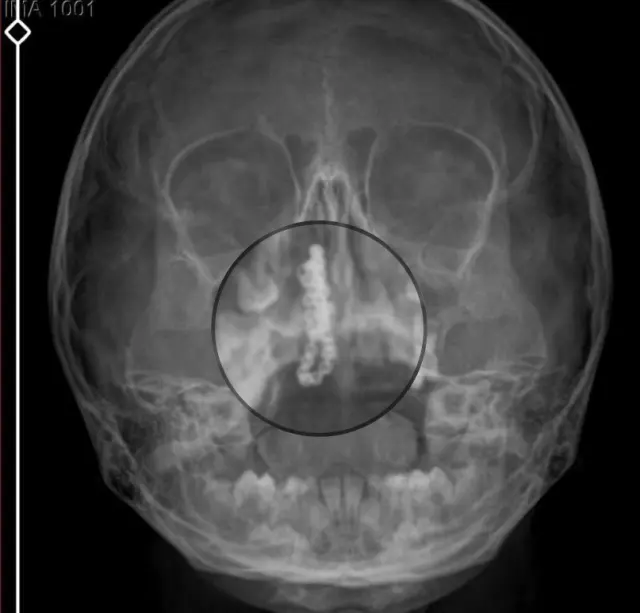

Devlet hastanesindeki doktorun incelemesi ve kapsamlı röntgen çekilmesi sonrası Polen’in burnunda metal cisim olduğu fark edildi. 2 yıldır burunda kaldığ

değerlendirilip, küçük top şeklinde tırnak makası zinciri olduău belirlenen cisim, başarılı ameliyatla çıkarıldı. Bir süre tedavisi sürdürülen Polen, sağlığına kavusunca taburcu edildi. Özel hastane yetkilileri, konuyla ilgili açıklama yapmazken; aile suç duyurusunda bulunacaklarını söyledi.

Kızının burnundan sürekli sivah renkte akıntı olduğunu anlatan Gökhan Tekin, Çocuğumun burnundan kanama ile sürekli siyah akıntı geliyordu. Özel hastaneye götürdüm. Özel hastanede film çekildi hiçbir bulguya rastlanılmadığı söylendi. sivah leke de enfeksiyona davalı olan bir şey olduğu bize söylendi. Eve geldik, akıntr sürmesi üzerine bu kez devlet hastanesine basvurduk. Burunda metal zinciri fark ettiler. Böyle bir ihmalkarlık olabilir mi? Özel hastaneye gidiyoruz, paramızla rezil oluyoruz. Zincir, 2 yıldır burnunda ve devletimizin hastanesinde iyi bir doktorumuz zinciri ortaya çıkarıyor, kızım ölümden dönüyor. Ben sonuna kadar bu işin peşini bırakmayacağım. Sonuna kadar hukuk mücadelesi vereceðim. Bu da diğer hastalarımıza ibret olsun. Iste, bakın koca bir zincir. ‘Bulguya rastlanılmadı’ deniliyor’

Kizının ameliyat sonrası durumunun iyi olduğunu söyleyen Tekin, “İnanır mısınız bize ‘Evde soba mı yanıyor? Acaba kömür isten dolayı mıdır bu?’ dendi. Böyle bir sey olabilir mi? Ameliyattan çıkan parmağım kadar zincir. Devlet hastanesindeki doktor da `’Bu nasıl gözden kaçılabilir? Böyle bir pozisyon nasıl görülmeyebilir?’ yorumunda bulundu. Allah’a sükür olsun atlattık. Su anda durumu, vaziyeti iyidir. Ben suna inanıyorum doktor da bir sans isidir. Bakın paramızla özele gideriz ya hani bizde, daha jyi ilgilenirler. Oysa devlet hastanesindeki doktorumuz olayı meydana çıkardı” diye konuştu.